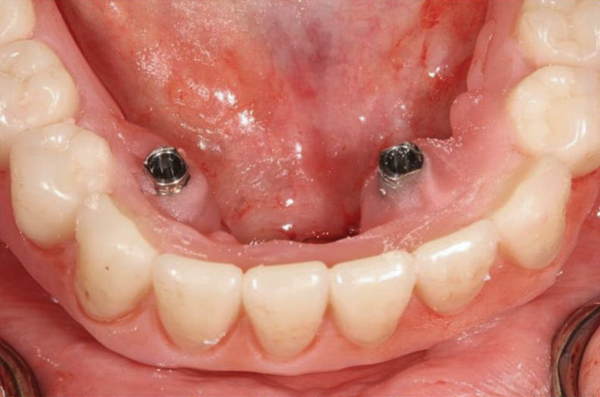

Fig 18. The patient’s intraoral condition.

Figure 18

Fig 19. Patient smile shown 3 years post-treatment.

Figure 19

Fig 20. Patient intraoral condition 3 years following delivery of maxillary and mandibular All-on-4 definitive prosthesis.

Figure 20